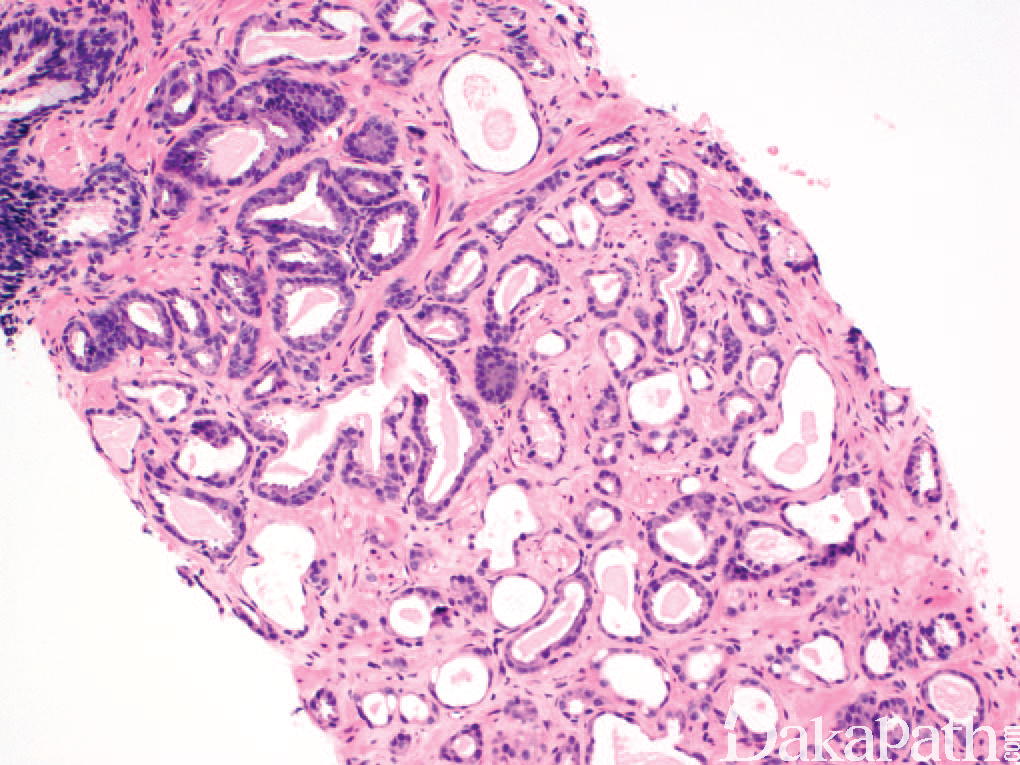

- 呈小叶状构型,界限清楚。一些良性萎缩病例的特征性表现为中心是扩张的萎缩性腺体,周围可见丛状、较小的腺体围绕,这种病变称为“萎缩后增生(PAH)。虽然在穿刺活检标本中,良性萎缩的腺体可呈类似浸润性表现,但在较大的良性腺体间不会见到个别浸润性生长的良性萎缩性腺体,因此其并非真正的浸润;

- 某些良性萎缩可伴有腺体之间的纤维组织增生,而萎缩型前列腺癌没有这种组织学改变;

- 核缺乏明显的非典型性,良性萎缩时细胞核可增大,可有小而明显的核仁,一般核仁的明显程度不如萎缩性前列腺腺癌;

- 免疫组织化学染色:基底细胞标记阳性,AMACR 阴性等可与萎缩型癌鉴别。